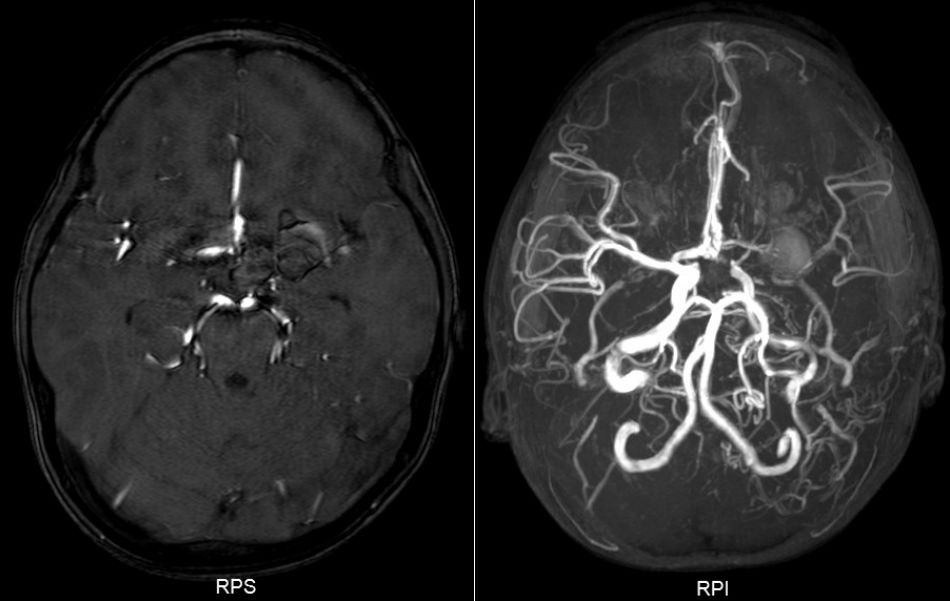

患儿术后情况良好,无对侧肢体偏瘫及其他脑缺血并发症。术后1周复查MRA,提示左侧大脑中动脉M1及大脑前动脉A1段显示欠清,瘤体仍大小相仿(图5)。出院继续随访。

图5. 术后1周MRA,显示左侧A1和M1纤细,动脉瘤影变淡。

术后1月复查MRA提示:动脉瘤体内类似血栓形成,中动脉周围可见细小侧枝循环血管形成,中动脉远端血管稀疏(图6)。

图6. 术后1月MRA,动脉瘤体内类似血栓形成,中动脉周围可见细小侧枝循环血管形成,中动脉远端血管稀疏